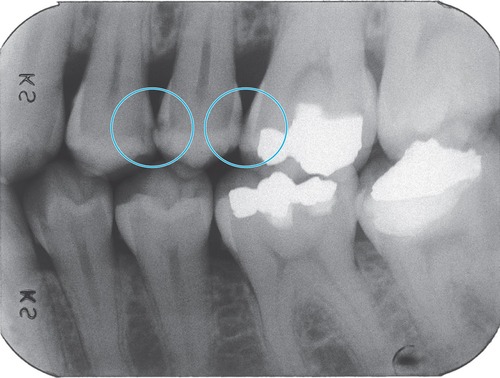

Your Enamel Is Under Constant Attack

Every beverage you consume creates an acid challenge in your mouth. A peer-reviewed study in the Journal of the American Dental Association tested 379 beverages available in the U.S. and found that 93% had a pH below 4.0 — well below the critical enamel dissolution threshold (Reddy et al., JADA, 2016; PMID: 26653863). A PRISMA-compliant systematic review of 19 studies confirmed that habitual consumption of carbonated acidic beverages causes structural disintegration and reduction of enamel's physical and mechanical properties (Cataldo et al., Nutrients, 2023; PMID: 37049624).

The demineralization process dissolves hydroxyapatite crystals — the mineral backbone of enamel — releasing calcium and phosphate ions. Once enamel is lost, it does not regenerate. This is not cosmetic damage. It is irreversible structural loss.

The Erosion Reality

What Your Favorite Drink Is Really Doing

Peer-reviewed research reveals the hidden damage of everyday beverages — and why EA Enamel Actives™ changes everything.